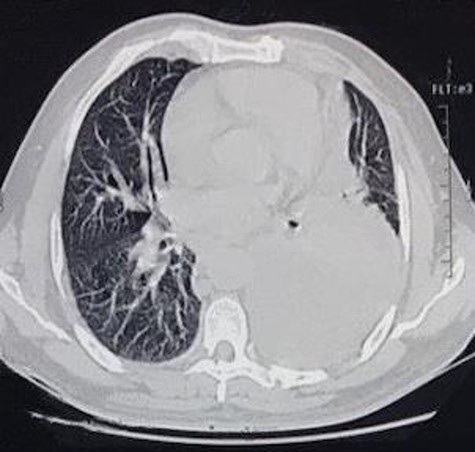

The first case consists of a 26-year-old male that presented with dyspnoea at rest, tachycardia, jugular vein distention, and slight facial and upper limb edema. The patient had been previously treated with ceftriaxone and moxifloxacin, and underwent a left thoracostomy due to a chest radiograph that showed a pleural effusion in the left inferior hemithorax. At auscultation, the patient had reduced air entry in the left lung base. The patient did not show improvement with the treatment previously given, so new laboratory tests were ordered. The blood test showed an elevated lactate dehydrogenase at 652 U/L and the pleural fluid analysis showed an elevated lactate dehydrogenase at 911 U/L, cholesterol level at 46 mg/dl, and triglyceride level at 847 mg/dl. According to these results, the pleural effusion was classified as an exudate. The high triglyceride level was consistent with a chylous effusion. A chest CT confirmed a pericardial effusion, the previously noticed free pleural effusion, and an irregular mass in the anterior mediastinum with heterogeneous density that included hypodense areas that suggest necrosis (Figs 1 and 2). Subsequently, the patient underwent surgical treatment, which consisted of a pericardial window. Aside from this procedure, the anterior mass was biopsied. Histological analysis revealed a non-Hodgkin lymphoma. Due to the diagnosis, the patient was transferred to the hematology care unit to receive chemotherapy, but he continued to deteriorate and passed away 2 months later.

CT scan axial view of a pericardial and left lung pleural effusion.